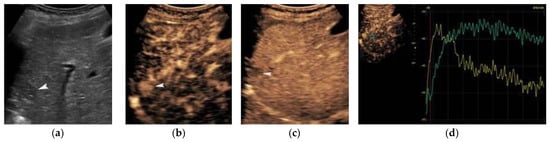

The vascularity of a FLL is important, pointing towards a benign or malignant diagnosis. From a technical point-of-view, colour Doppler is the first-line modality to assess for intratumoral or peripheral vascularity, but it suffers from technical limitations such as Doppler-angle-dependence, low sensitivity to slow flow, and overwriting artifact. Power Doppler and modern non-Doppler flow visualization techniques are now available for improved characterization of HCC vascular architecture. HCCs less than 2 cm commonly appear avascular due to the technique’s low sensitivity, while in some cases blood vessels are visualized as lines or dots inside, or surrounding, the tumor. A continuous waveform on spectral analysis can be seen in these tumors, in keeping with feeding portal flow. Once the tumor increases in size, more characteristic vascular patterns can be appreciated. Namely, the “basket” pattern of vascularity refers to the presence of a fine network of arterial branches surrounding the lesion. Using spectral analysis, both pulsatile and continuous waveforms can be recorded, which correspond to the hepatic artery and hepatic or portal vein origin of blood supply, respectively. In the massive-type HCC, an overall irregular pattern of vascularity can be appreciated [

9]. As a general rule, a continuous (portal vein-like) waveform indicates a dysplastic nodule or a well-differentiated HCC; contrarily, a pulsatile arterial waveform is suggestive of advanced HCC [

14]. Power Doppler tends to detect intratumoral colour signals in 19% or more of angiographically hypervascular lesions compared to colour Doppler. Tumors appearing hypovascular on angiography typically exhibit no flow signals on either colour or power Doppler. Power Doppler is less affected than colour Doppler by the small size and the deep tumor location [

15]. HCCs with a higher resistive and pulsatility index were associated with early recurrence, suggesting a more malignant nature [

16].